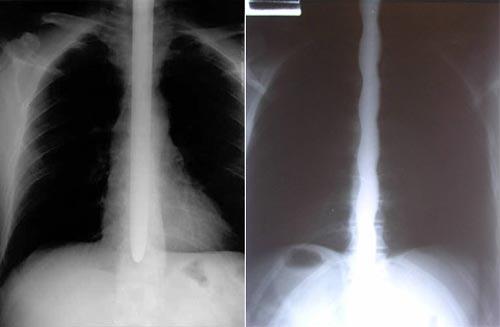

Без слов понятно, что глотание шпаг – рискованное дело. Но насколько рискованное? Нашлись люди, которые решили выяснить это поточнее - разобраться, к каким последствиям может привести такое хобби, или способ заработка…

Некоторые шпагоглотатели жалуются на боль в нижней части груди. Причём она длится у них несколько дней. Всё что нужно для лечения – воздержаться от глотания шпаг до полного выздоровления.16 из проанкетированных человек полагают, что они травмировали кишечник в результате своих «острых» занятий, а один даже уверен в том, что поцарапал себе лезвием сердце.

Некоторые обращались за хирургической помощью. Причём их травмы были вызваны какими-то уж чересчур изощрёнными манипуляциями. Так, один глотатель серьёзно порезал глотку, пытаясь проглотить сильно изогнутую саблю. А другой травмировал пищевод – попугай, сидевший во время представления у шпагоглотателя на плече, вдруг начал как-то дурно себя вести, чем и предрёк трагический исход шоу.

Ещё одна серьёзная травма случилась из-за того, что во время представления зритель попытался засунуть деньги за пояс трюкачке, которая с тремя проглоченными саблями исполняла танец живота ! Много ли было денег – не сообщается. Но известно, что в итоге лезвия неким образом сработали как ножницы, результатом чего стало сильное кровотечение…

Что же касается прочих «отчётов» испытуемых, то исследователи полагают, что в целом внешние симптомы могут быть преувеличены, а внутренние преуменьшены — у многих наверняка есть и не выявленные внутренние повреждения.